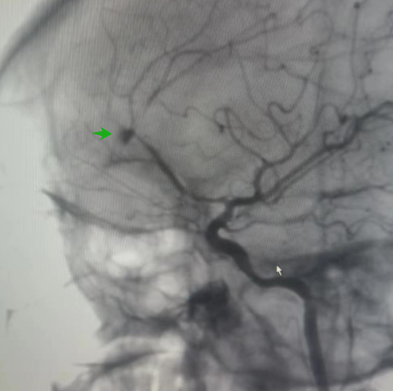

因患者突发症状加重,神经外科二区立即启动疑难病例讨论,经分析,患者颅内外伤40余天,再迟发出血,出血原因不明,此出血位置与大脑前动脉邻近,不排除外伤导致的颅内假性动脉瘤破裂,进一步行颅脑CTA检查提示:右侧大脑前动脉A1段缺失、双侧A2共干,A2远端重度狭窄并出现囊瘤样突出,大小约4mmx7mm。

▲CTA可见瘤样病灶

由此可以明确出血原因:车祸时出现载瘤动脉损伤(大脑前动脉胼周段),在血流动力学影响下损伤血管壁不断囊性扩大,最后破裂出血,并出现相关临床表现。此类情况患者病情危急,需尽快治疗,以免大出血危及生命。

▲DSA下瘤体显影不完全

经神经外科介入手术团队充分知情告知、签字同意后,紧急启动治疗方案:全麻下实施脑血管造影及血管内治疗。脑血管造影(DSA)显示瘤体显影不完全,我们称之为“鬼影”或“幽灵”动脉瘤,是创伤性动脉瘤的显影特征,提示瘤体不稳定、易破裂出血。